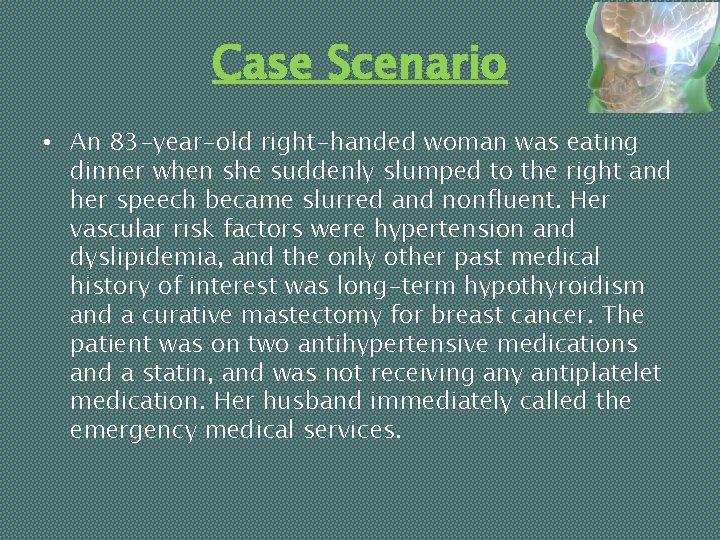

Case Scenario • An 83 -year-old right-handed woman was eating dinner when she suddenly slumped to the right and her speech became slurred and nonfluent. Her vascular risk factors were hypertension and dyslipidemia, and the only other past medical history of interest was long-term hypothyroidism and a curative mastectomy for breast cancer. The patient was on two antihypertensive medications and a statin, and was not receiving any antiplatelet medication. Her husband immediately called the emergency medical services.

Case Scenario On Examination Pulse is 84/min (regular), BP: 180/105 mm Hg. Angle of mouth is deviated towards left (UMN type Right 7 th CN) Tone is decreased in right upper and lower limb, Power is 2/5 in right upper and lower limb, Reflexex are absent in right upper and lower limb. Right Planter is upgoing. Tone, power, reflexes are normal on left side with downgoing planter What is your Diagnosis? ?

STROKE This patient has had STROKE causing Right sided uncrossed Hemiplegia with UMN type Facial Nerve Palsy which can be caused by a vascular event such as thrombosis, embolism or hemorrhage or by neaplasm of brain (aetiology). The patient is limited by hemiplegia (functional status)